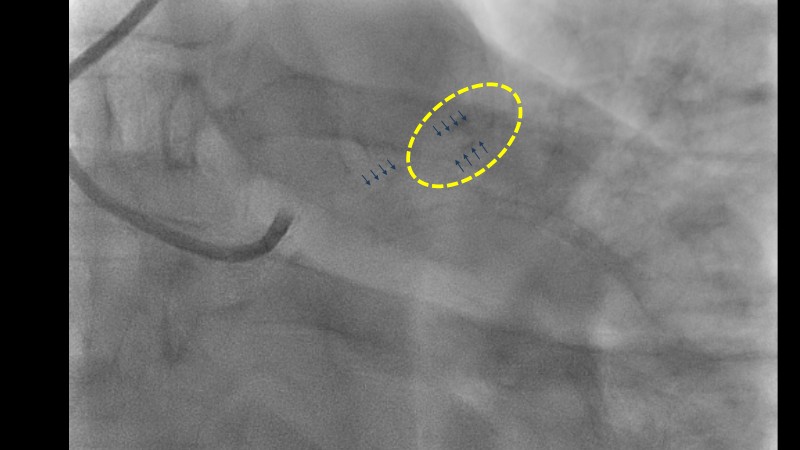

Explore the management of heavily calcified LAD lesions in this PCRGulf-GIM 2025 session. Discover how OCT imaging guides lesion assessment, differentiates superficial from deep calcium, and informs the need for plaque modification. Learn when and how to use orbital atherectomy or intravascular lithotripsy, and follow the step-by-step stent implantation, optimisation, and final evaluation using both angiography and OCT.

- To learn about the role of OCT imaging in the management of complex calcified coronary artery lesions.

- To learn indications of calcium modification using orbital atherectomy or other modalities, based on findings on OCT images.

- To learn the optimization of DES expansion by OCT in a complex calcified lesion.